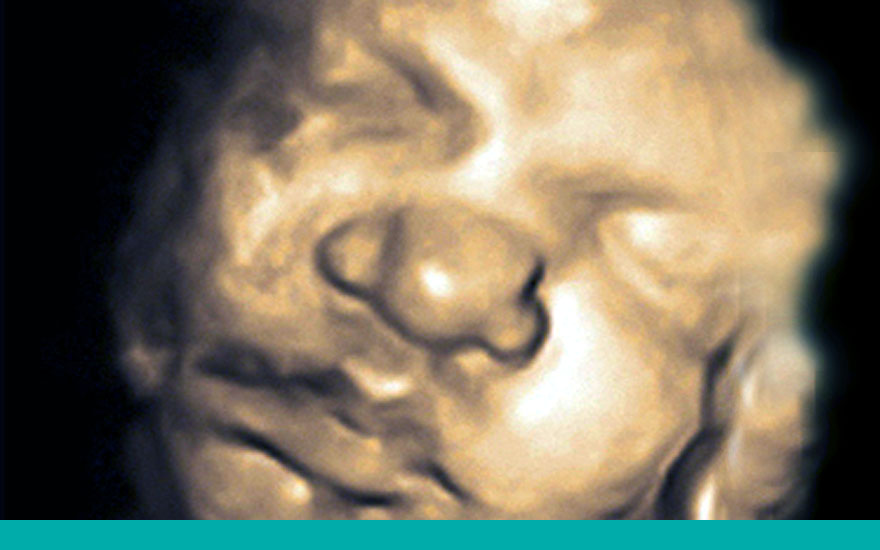

Cambios fisiológicos del bebé durante el tercer trimestre de gestación

Al final del segundo trimestre todos los órganos y partes del cuerpo de su bebé se han formado y funcionan correctamente. Ahora todo tiene que crecer y madurar.